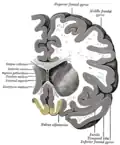

![]() Глазничная поверхность левой лобной доли | |

Коронарный срез мозга, прямая извилина отмечена жёлтым (внизу по центру)- Нижняя проекция мозга